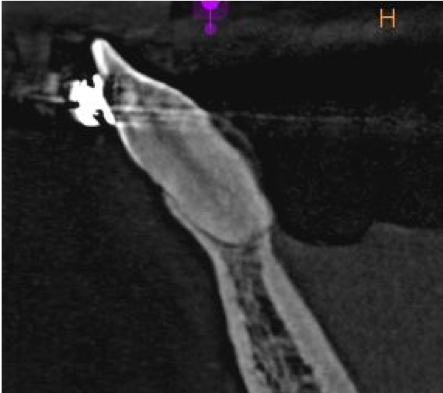

Pacjentka wiek: 26 l.

Badanie z dnia: 19.02.2019

CBCT wycinkowe żuchwy.

Pacjentka w trakcie leczenia chirurgicznego -płytka i śruby w okolicy bródkowej oraz ortodontycznego.

Zęby poddawane mechanoterapii ortodontycznej wykazują zmiany:

Ząb 31 zaawansowana resorpcja wewnętrzna prowadząca do zmniejszenia grubości struktur zęba a tym samym obniżenia jego wytrzymałości .W obrazie widoczne złamania patologiczne korzenia -szczeliny złamania przechodzące na poziomie ogniska resorpcyjnego.